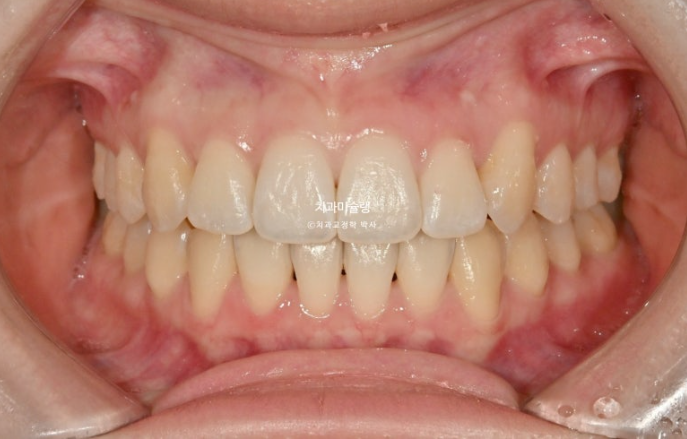

25.11

중심선 불일치가 미세하게 남았지만 만족스럽게 개선되었으며

어금니 교합은 좋습니다.

이제 전후 비교 보겠습니다.

치료기간은 10개월 입니다.